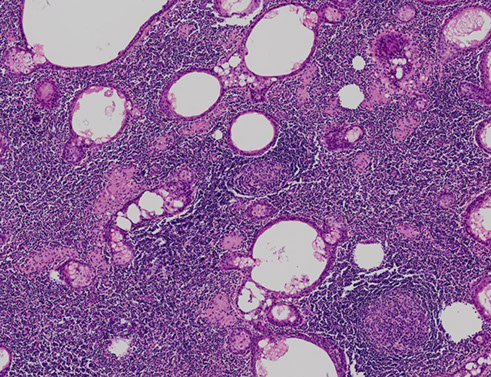

Oncocytosis

- aka multinodular oncocytoma, multifocal adenomatous oncocytic hyperplasia

Either parotid cysts lined by oncocytes or well defined clusters of oncocytes

- b9, multifocal / nodular or diffuse prolif of oncocytic cells usually in parotid gland (can be bilateral)

Oncocytoma